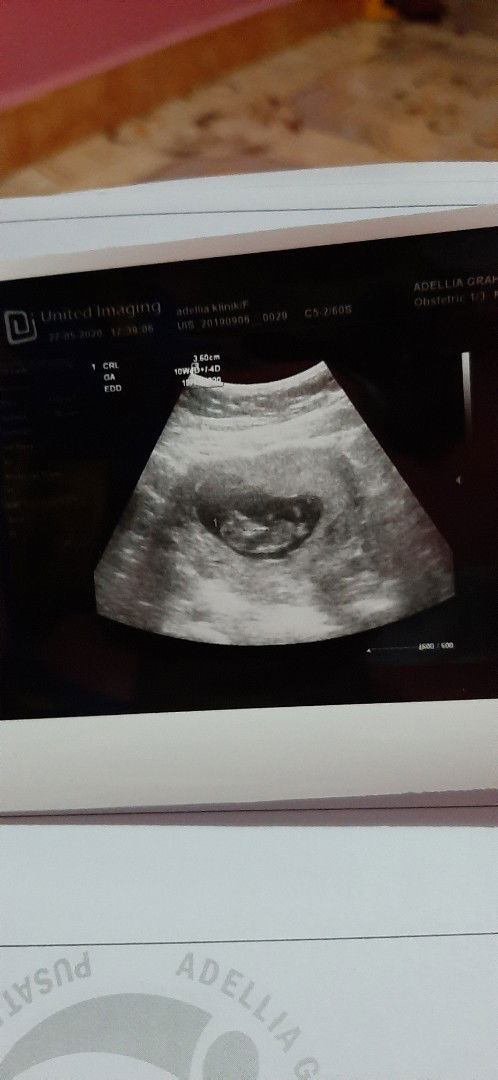

Baca lagiPada umumnya jenis kelamin bisa di lihat pada usia kandungan 5 bulan ke atas bund melalui USG, tapi ada sebagian bunda yang 4 bulan udah kelihatan dari USG jenis kelamin nya.... Pribadi aku, aku dari usia 3 bulan alhamdullilah hasil usg udah menunjukan untuk.jenis kelamin ya karna si baby gak malu malu untuk nampakin jenis kelamin nyaπππ

Baca lagiPas di usg kelihatan ntar tu bun, kalau palai 4D lebih jelas.. kadang jenis kelaminnya masih di sembunyikan janinnya bun, karna tertutup pahanya.. ntar terlihat dari 17 minggu ke atas bun

tanya dokternya bun mulai dr minggu ke 14 sdh bs ditanyakan setiap usg. kl saya wktu usg 15 minggu sdh kliatan jelas JK nya. tergantung alat usgnya dan posisi debay nya bun.

Mulai 10w bisa tes darah untuk tau jenis kelamin & mendeteksi kelainan kromosom pada janin . Kalau usg mulai dari 15w & tergantung posisi janin jg .

Nanti kalo sudah lebih besar udah bisa keliatan lebih jelas jenis kelaminnya, tapi tergantung posisi bayinya juga sih kehalangan atau gak

kl segimi masih belum kelihatan bun.. saya dulu usia 5-6bulan baru mau nunjukin JKnya dan itu dojter yang tau. bukan sembarang orang

Kan itu masih kecil bun Masih proses juga pembentukan kelaminnya si dede bayi Nanti kalau sudah sekitar 6 bulan keliatan jknya

10w masih belum keliatan kalo pake usg. Kalo mau pake tes kromosom, udah bisa tau jk nya. Tapi biayanya belasan juta.

aku pas 17weeks dah kelihatan bun jelas banget, kalau babynya cowo biasanya cepat kelihatan dari pada cewe bun